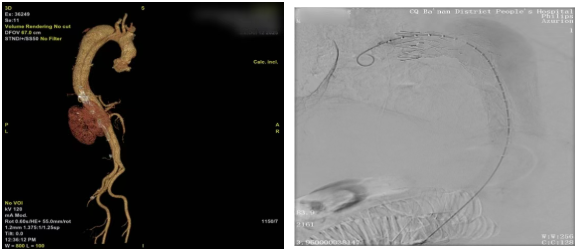

短暂的术后稳定期内,麻醉监护团队将患者血压精准控制在安全区间,为下一阶段手术筑牢基础。随后,甲状腺乳腺血管外科文飞主任医师、段成主治医师接力开展“胸主动脉覆膜支架腔内隔绝术”。术中,医护团队精准操控输送系统,将覆膜支架成功释放于降主动脉夹层破口处,完美覆盖原发撕裂口。术后造影证实,破口封堵满意,假腔血流显著减少,真腔及重要分支血管血供完好,第二阶段手术同样圆满成功。

▲甲状腺乳腺血管外科手术造影显示破口封堵满意